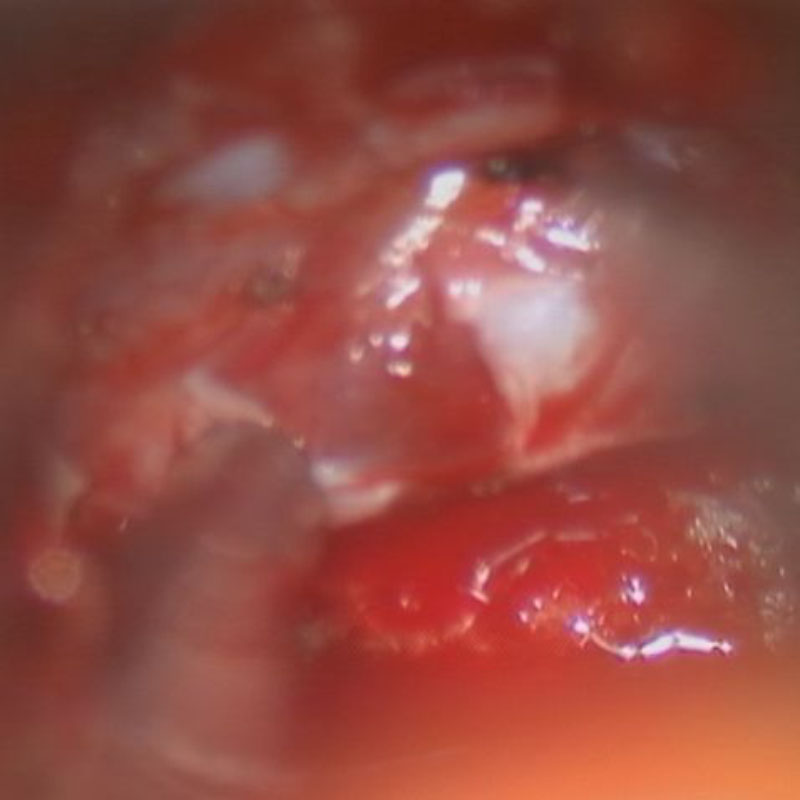

517

'24年3月

10代

小脳血管芽腫

頭蓋内腫瘍摘出術

No.’24_19 手術前1

No.’24_19 手術前2

No.’24_19 摘出 前

No.’24_19  摘出 中

No.’24_19 摘出 後